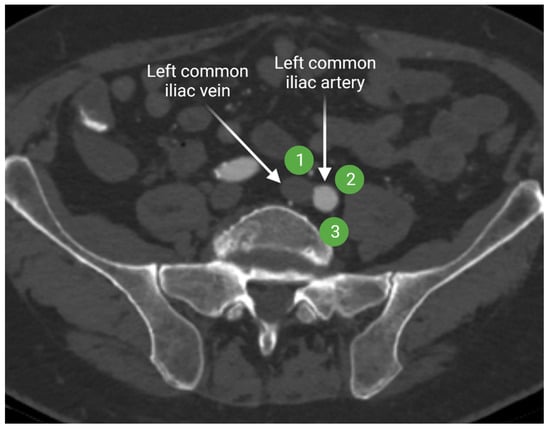

2.1.2. Iliac Lymph Nodes Anatomy

4.1.2. Computed Tomography (CT) and Conventional Magnetic Resonance Imaging (MRI) of the Lymphatic System